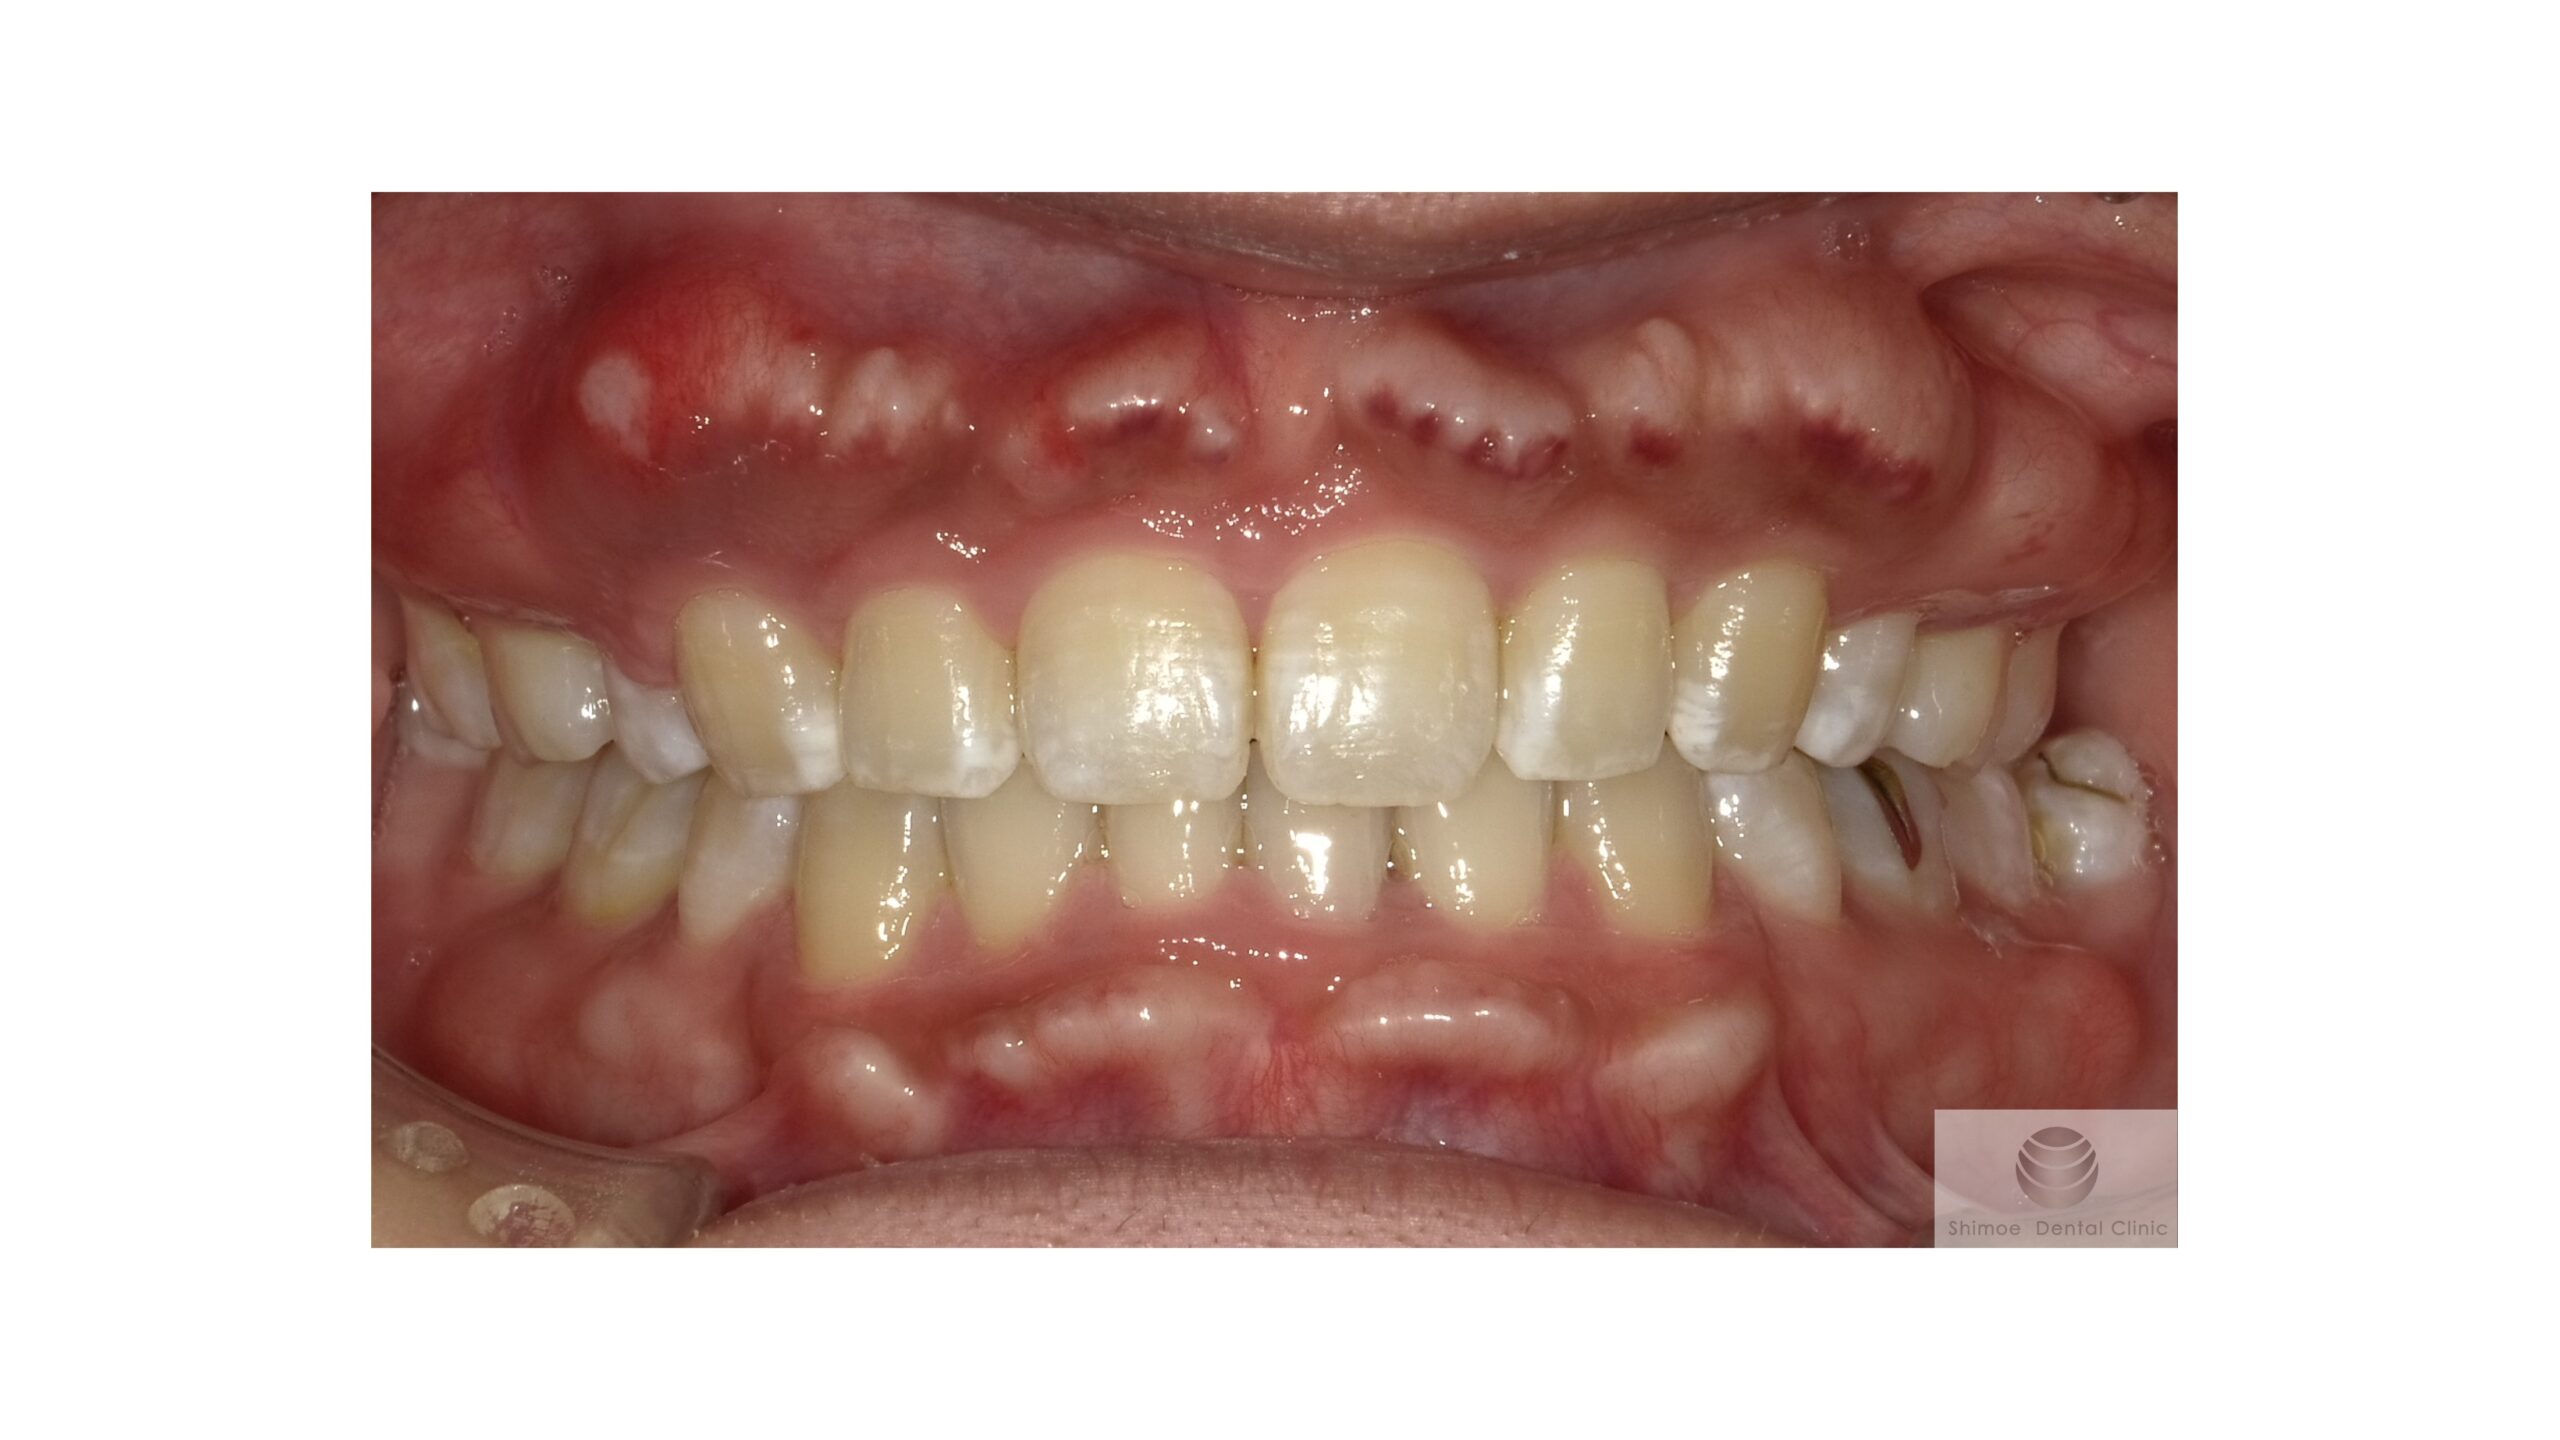

初診時

初診時の口腔内写真です。